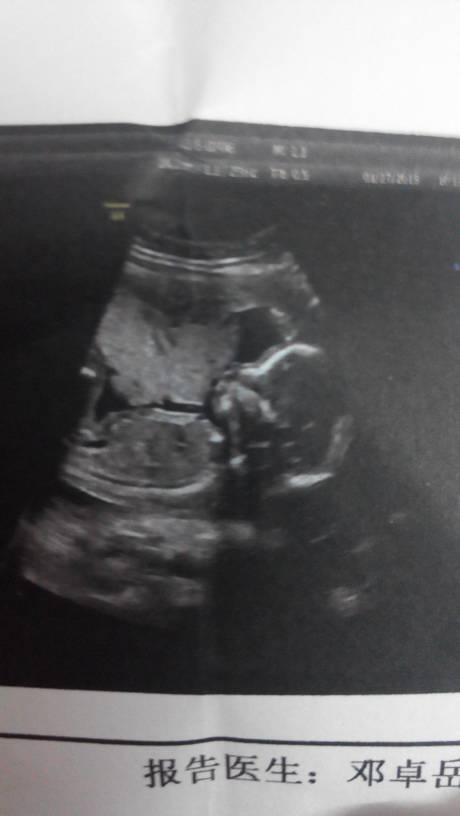

18周5天怎么知道胎儿的健康问题,比如心跳率或者胎儿的形状等等的? 18周5天怎么知道胎儿的健康问题,比如心跳率或者胎儿的形状等等的? 点击展开 未成年少女 2015-01-29 07:45 为您推荐: 其他回答 你好,做B超没事就没有问题的,现在宝宝太小,胎心监护做还太小了,可以去医院用多普勒听一下胎心音。 a_xinglixin808 2015-01-29 14:55 医生会和你说结果啊啊 希望没有 2015-01-29 09:04 等二十四周做四维就知道形状了 廖惜晨 2015-01-29 08:26 医生没说什么就是健康 轩凡麻麻 2015-01-29 08:08 问下医生毕竟放心 真知棒_GMXC 2015-01-29 07:51 加载更多 相关问题 孕11周如果想知道胎儿有没有心跳,不想做B超,号脉搏能号出怀孕就证明胎儿是正常的对吗 我怀孕38周了,胎监胎儿心跳过频,每分钟180左右,请问严重吗? 我现在怀孕14周,把手放在肚子上可以明显的感觉到规律的跳动,请问是胎儿的心跳么?